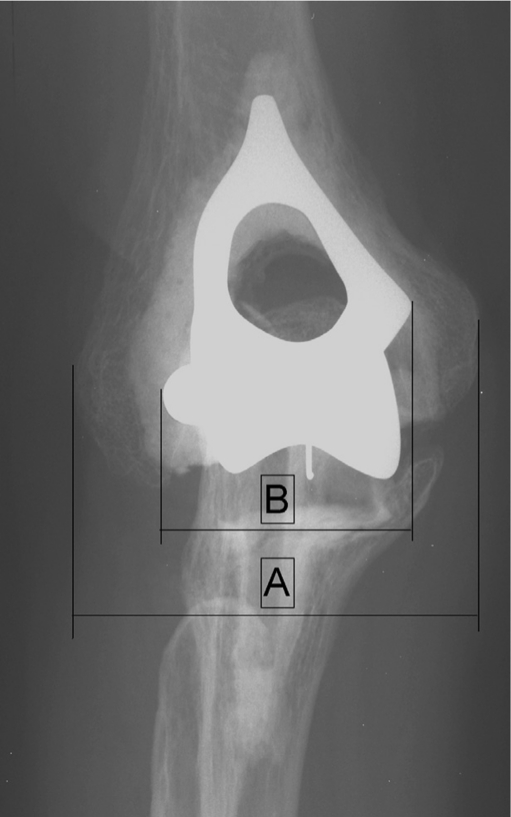

Fig. 2.

The ratio between the maximal width of the component (b) and the maximal width of the bone (a)